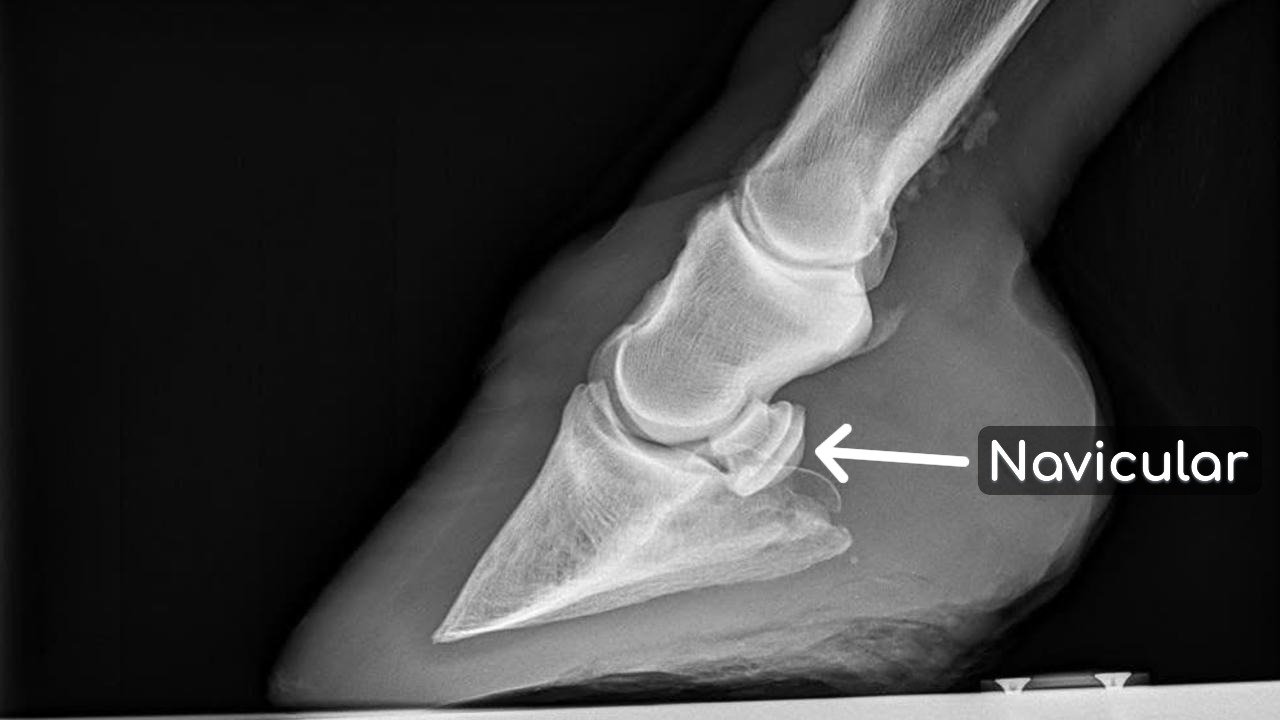

El síndrome navicular es una alteración dolorosa que afecta a los caballos, especialmente aquellos que realizan actividades físicas intensas, como en la equitación de competición. Esta condición tiene lugar en la estructura ósea conocida como hueso navicular, situada en la parte posterior del casco del caballo. La inflamación y el daño en esta área pueden provocar un dolor significativo, dificultando la movilidad y el rendimiento del animal.

El diagnóstico del síndrome navicular requiere una evaluación veterinaria exhaustiva. Esto puede incluir radiografías y pruebas de sensibilidad que ayudan a determinar la localización exacta del dolor. El manejo de esta condición puede variar; puede incluir modificaciones en la herradura, tratamientos médicos y, en algunos casos, cirugía. Los propietarios de caballos deben colaborar estrechamente con sus veterinarios para establecer un plan adecuado que ayude a aliviar el dolor y mejorar la calidad de vida del animal.